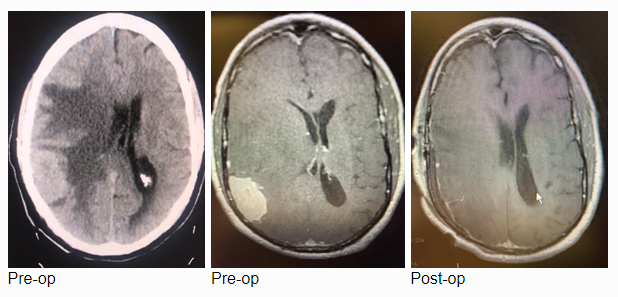

The patient is an otherwise healthy 80-year-old gentleman who presented with complaints of right frontal headaches and difficulty walking that had progressed over about three weeks. He was neurologically nonfocal. CT scan without contrast showed a large right parietal mass with midline shift and cerebral edema.

MRI with gadolinium confirmed the likely diagnosis of convexity meningioma, a benign neoplasm of the meninges. Given the location of the tumor, angiography and embolization were deemed unnecessary prior to resection. Stereotactic c-guided craniotomy was performed by Dr. Jonathan Brisman and the tumor was carefully excised from the surrounding brain. A gross total resection was achieved. He was discharged from the hospital to his home, neurologically intact with a slow improvement of his gait. Postoperative MRI showed no evidence of residual tumor.